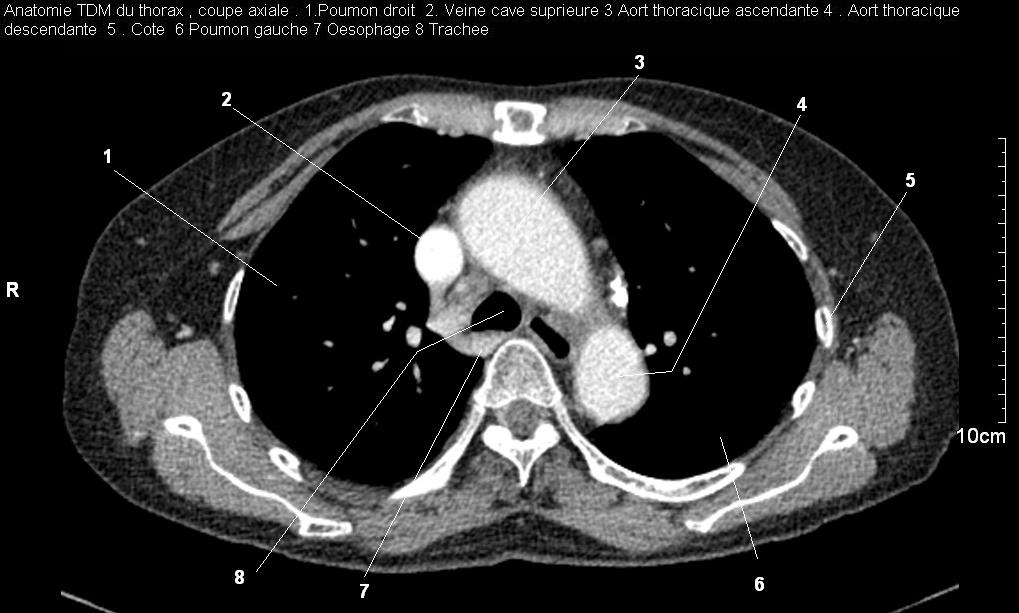

Radioanatomie pulmonaire ( image radiologie thoracique normale )- La Tomodensitometrie du  thorax ( coupes axiales fenetre mediastinale )

Les fenetres mediastinales permettre d'etudier anatomie du mediastin et les structures vasculaires en coupes axiales de 0,5-1cm sur le thorax . Et si elles sont opacifiees par produit de contrast elles sera se donnent des resutats suivantes :